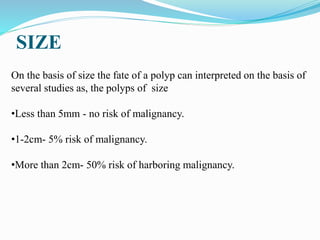

This document discusses colorectal polyps. It defines polyps and describes their types, including neoplastic and non-neoplastic polyps. It discusses adenomatous polyps in depth, noting their malignant potential increases with size over 1cm and villous architecture. Radiological diagnostic methods for polyps including single and double contrast barium enema and CT colonography are explained. The document provides an overview of polyp pathogenesis and genetic syndromes like FAP that increase cancer risk.